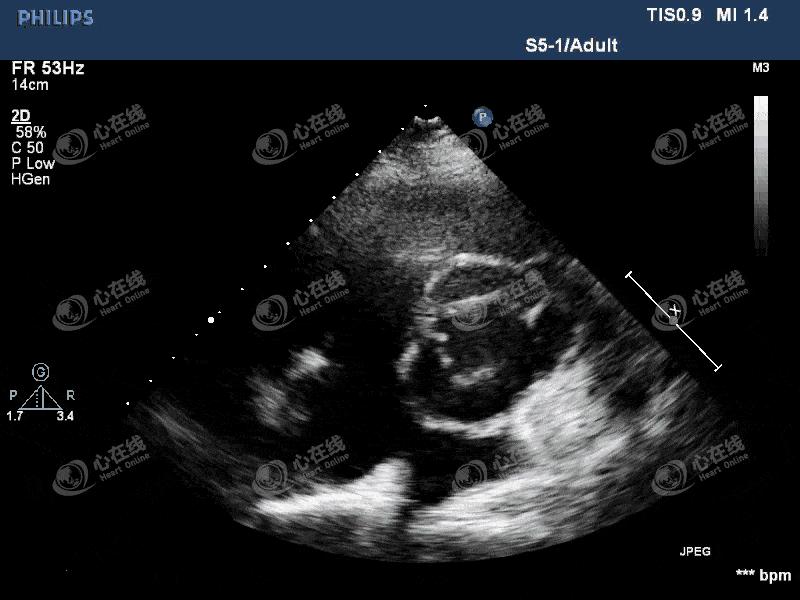

【超声心动图】

图4 大动脉短轴切面:主动脉瓣机械瓣缝合环外周可见蜂窝状无回声区环绕,机械瓣环活动度增大,机械瓣启闭正常。